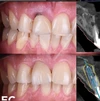

Empress Porselen Kaplama

Yaprak Porselen Lamina